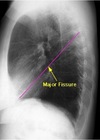

How well did you know this?

1